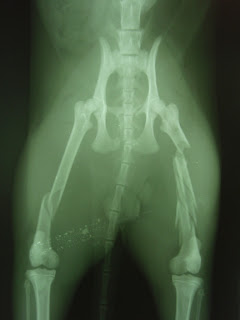

Infelizmente o quadro clínico dele inspira muitos cuidados pois tem os 2 fémures partidos e a bacia.

O fémur do lado direito está fracturado num sitio e o fémur do lado esquerdo tem multiplas fracturas. As fracturas da bacia são em locais que com o repouso adequado não necessitarão de cirurgia.

Envio fotos do mustafá internado e do raio X que comprova as fracturas.